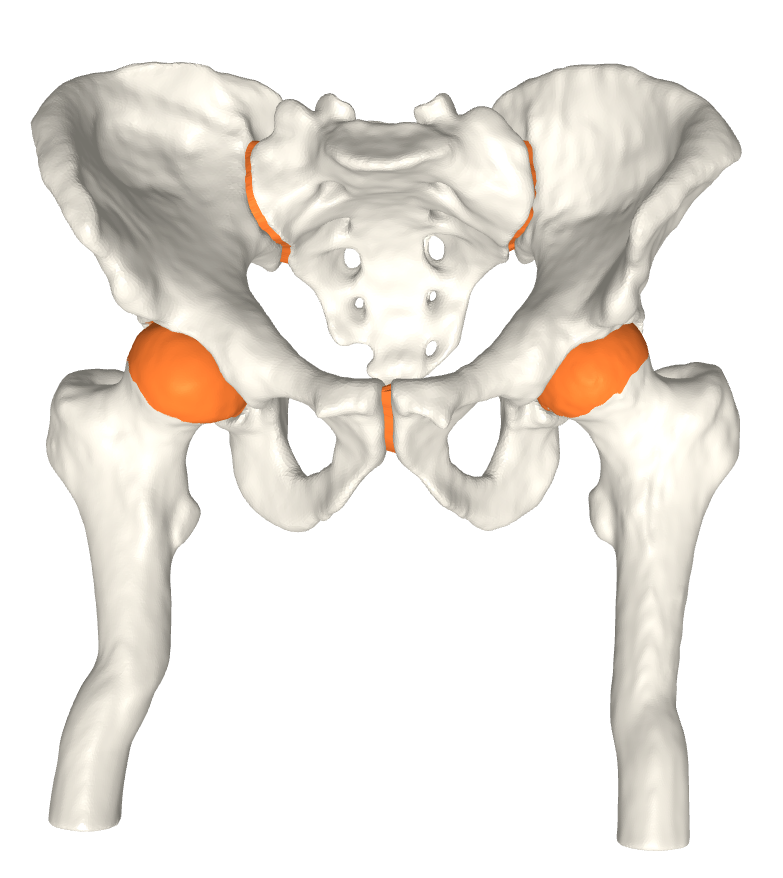

The FE analysis results show that the generated models produce smooth stress patterns in a pseudo stance without any geometry-related convergence issues. As mentioned in section 4, these results only serve as a verification test of simulation properties. We need a more advanced simulation setting to model a real stance position. We leave this for future work. Moreover, we believe that minor modifications will estimate the shoulder joint cartilage since it has a similar ball-in-socket structure. Fig. 5 shows early evidence of generalization. In contrast, other joints, such as the knee joint, are challenging. We leave other joint types for future work.

Refer to caption

(a)

(b)

(c)

Figure 5: a) All generated cartilages. Zoom boxes highlight the pubic and sacroiliac joint cartilages. b) Shoulder joint cartilage c) Femoral and tibial cartilage in the knee joint. Bone models are acquired from available datasets [3, 5, 4].